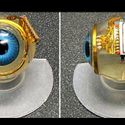

The Electric Eye: A Visual Prosthesis

10/26/10 A major breakthrough in the restoration of vision. Shawn Kelly

Bionic Being: The New Prosthetics

06/21/11 In this extraordinary era almost any limb, organ or tissue can be replaced. Shawn Kelly